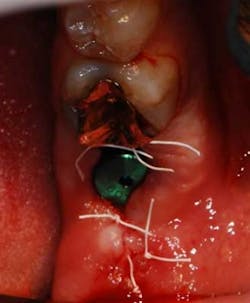

Fig. 5: Healing abutment placed and flap closed with sutures